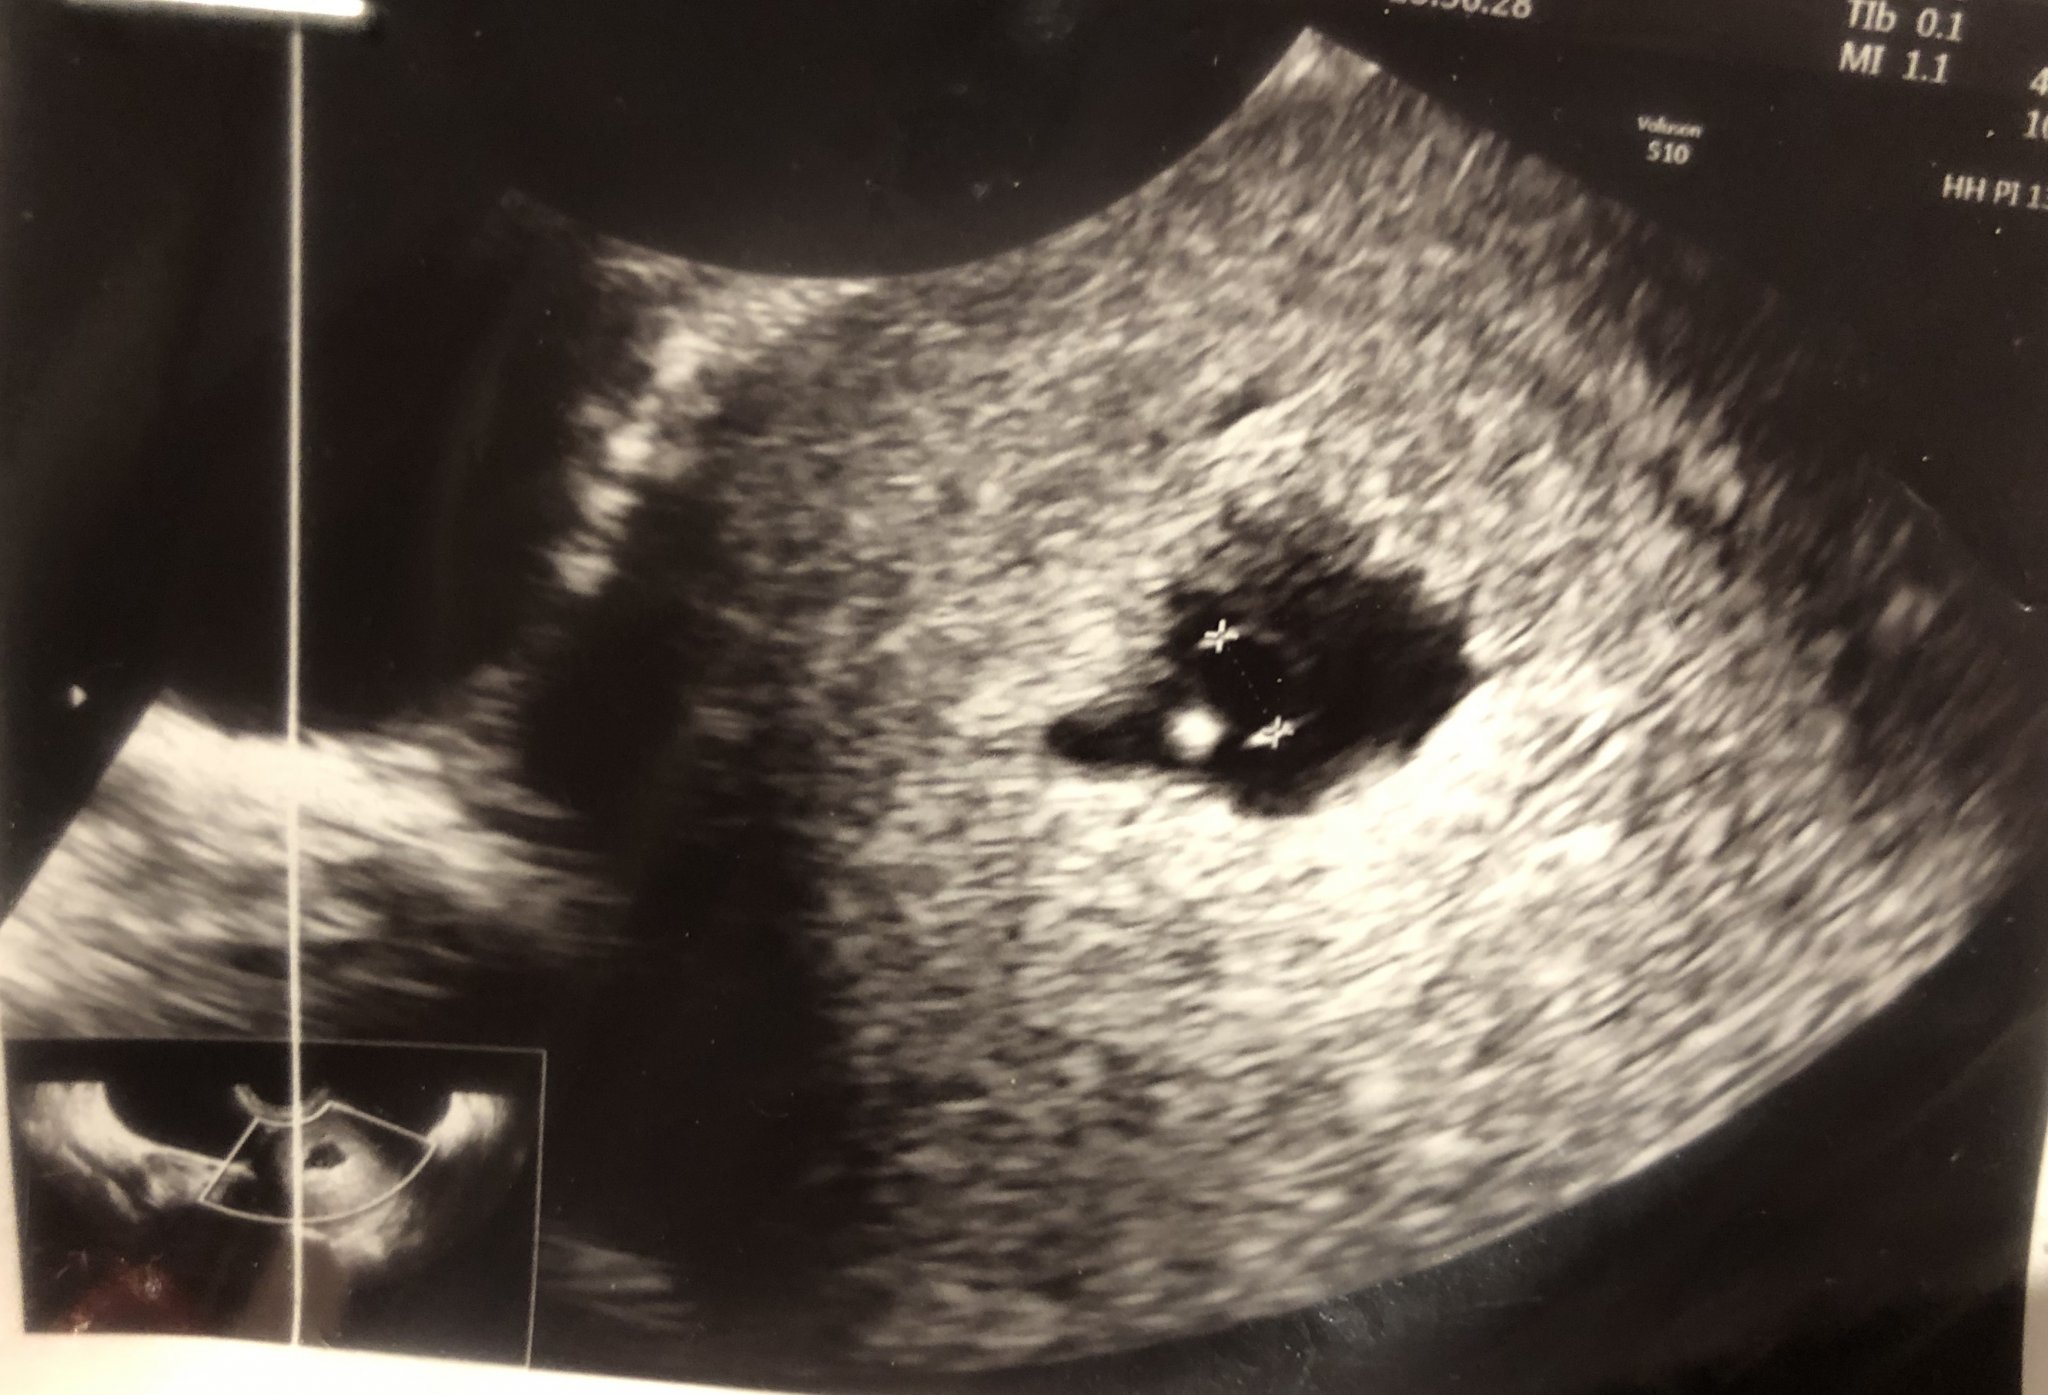

Ами сега си погледнах листа..прегледала ме е д-р Мария Атанасова-Еленкова.Също така искам да попитам какво мислите за формата на плодния сак,тъй като на мен лично ми изглежда малко странна?!

(7г.с + 3 дни)

Verji777 според мен отиди при друг лекар най-добре и не избързвай с прегледа,защото ако си била с късна овулация пак няма да има сърдечна дейност,все пак се развива и на мен ми се струва,че всичко ще е наред накрая,при някакви притеснения ходи на лекар,но след 3-4 дни ми се струва,че ще е рано пак.

Ии аз така мисля.

Другият вариант е да си преместя прегледа,но за кога не знам Neutral Face

Иначе съм избрала д-р Врагалева да ме следи от МЦ Фемина.Вчера ме гледаха просто извънредно заради вируса и се оказа,че има ембрион.